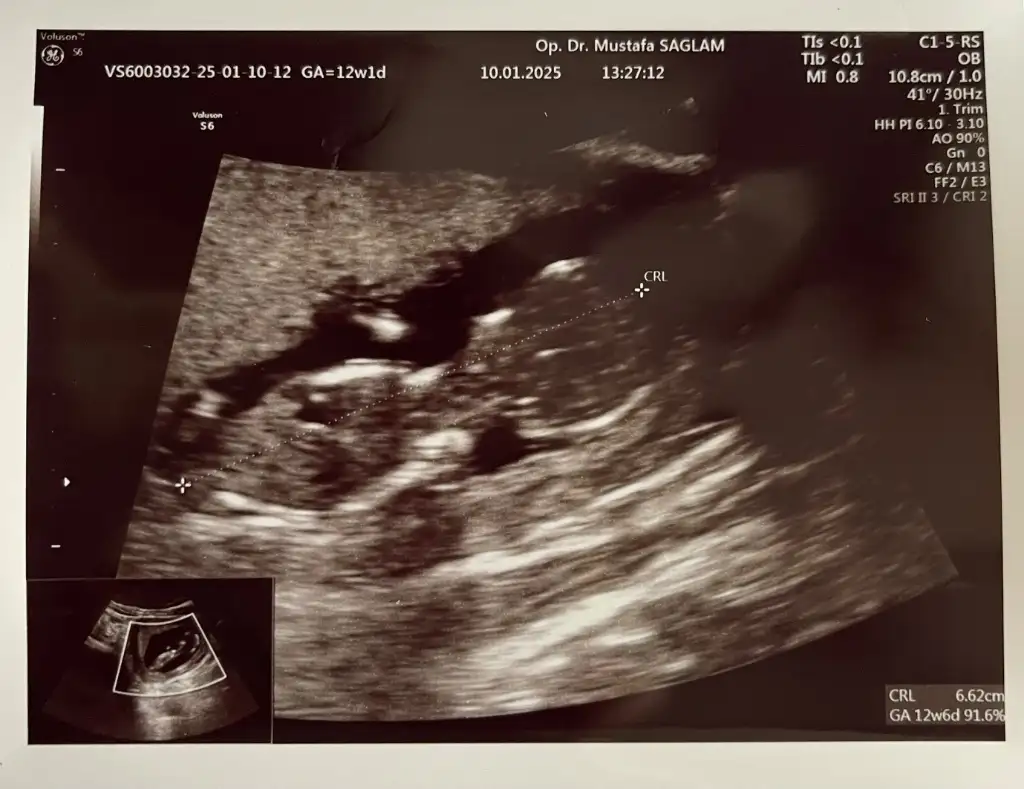

Birsey soracagim birde ben 12. Haftadan beri riskli gebelik takibi yapan bir doktora muayene oluyorum. Normalde diger takip eden doktorum perinatolog ile gorusmemi istemisti ama bu doktorum hic gerek olmadigni soyledi. Hatta 12. Haftada detayli ultrasonuda kendi yapti. 20/22 arasindaki detayliyida kendi yapacakmis. Perinatolojiye gitmene hic gerek yok ekstrem bir sorun cikmadigi surece ben sureci yonetebilecek bir hekimim diyor. Acikcasi cvsinede guvendim bu konuda. Ama yinede bir soru isaretim